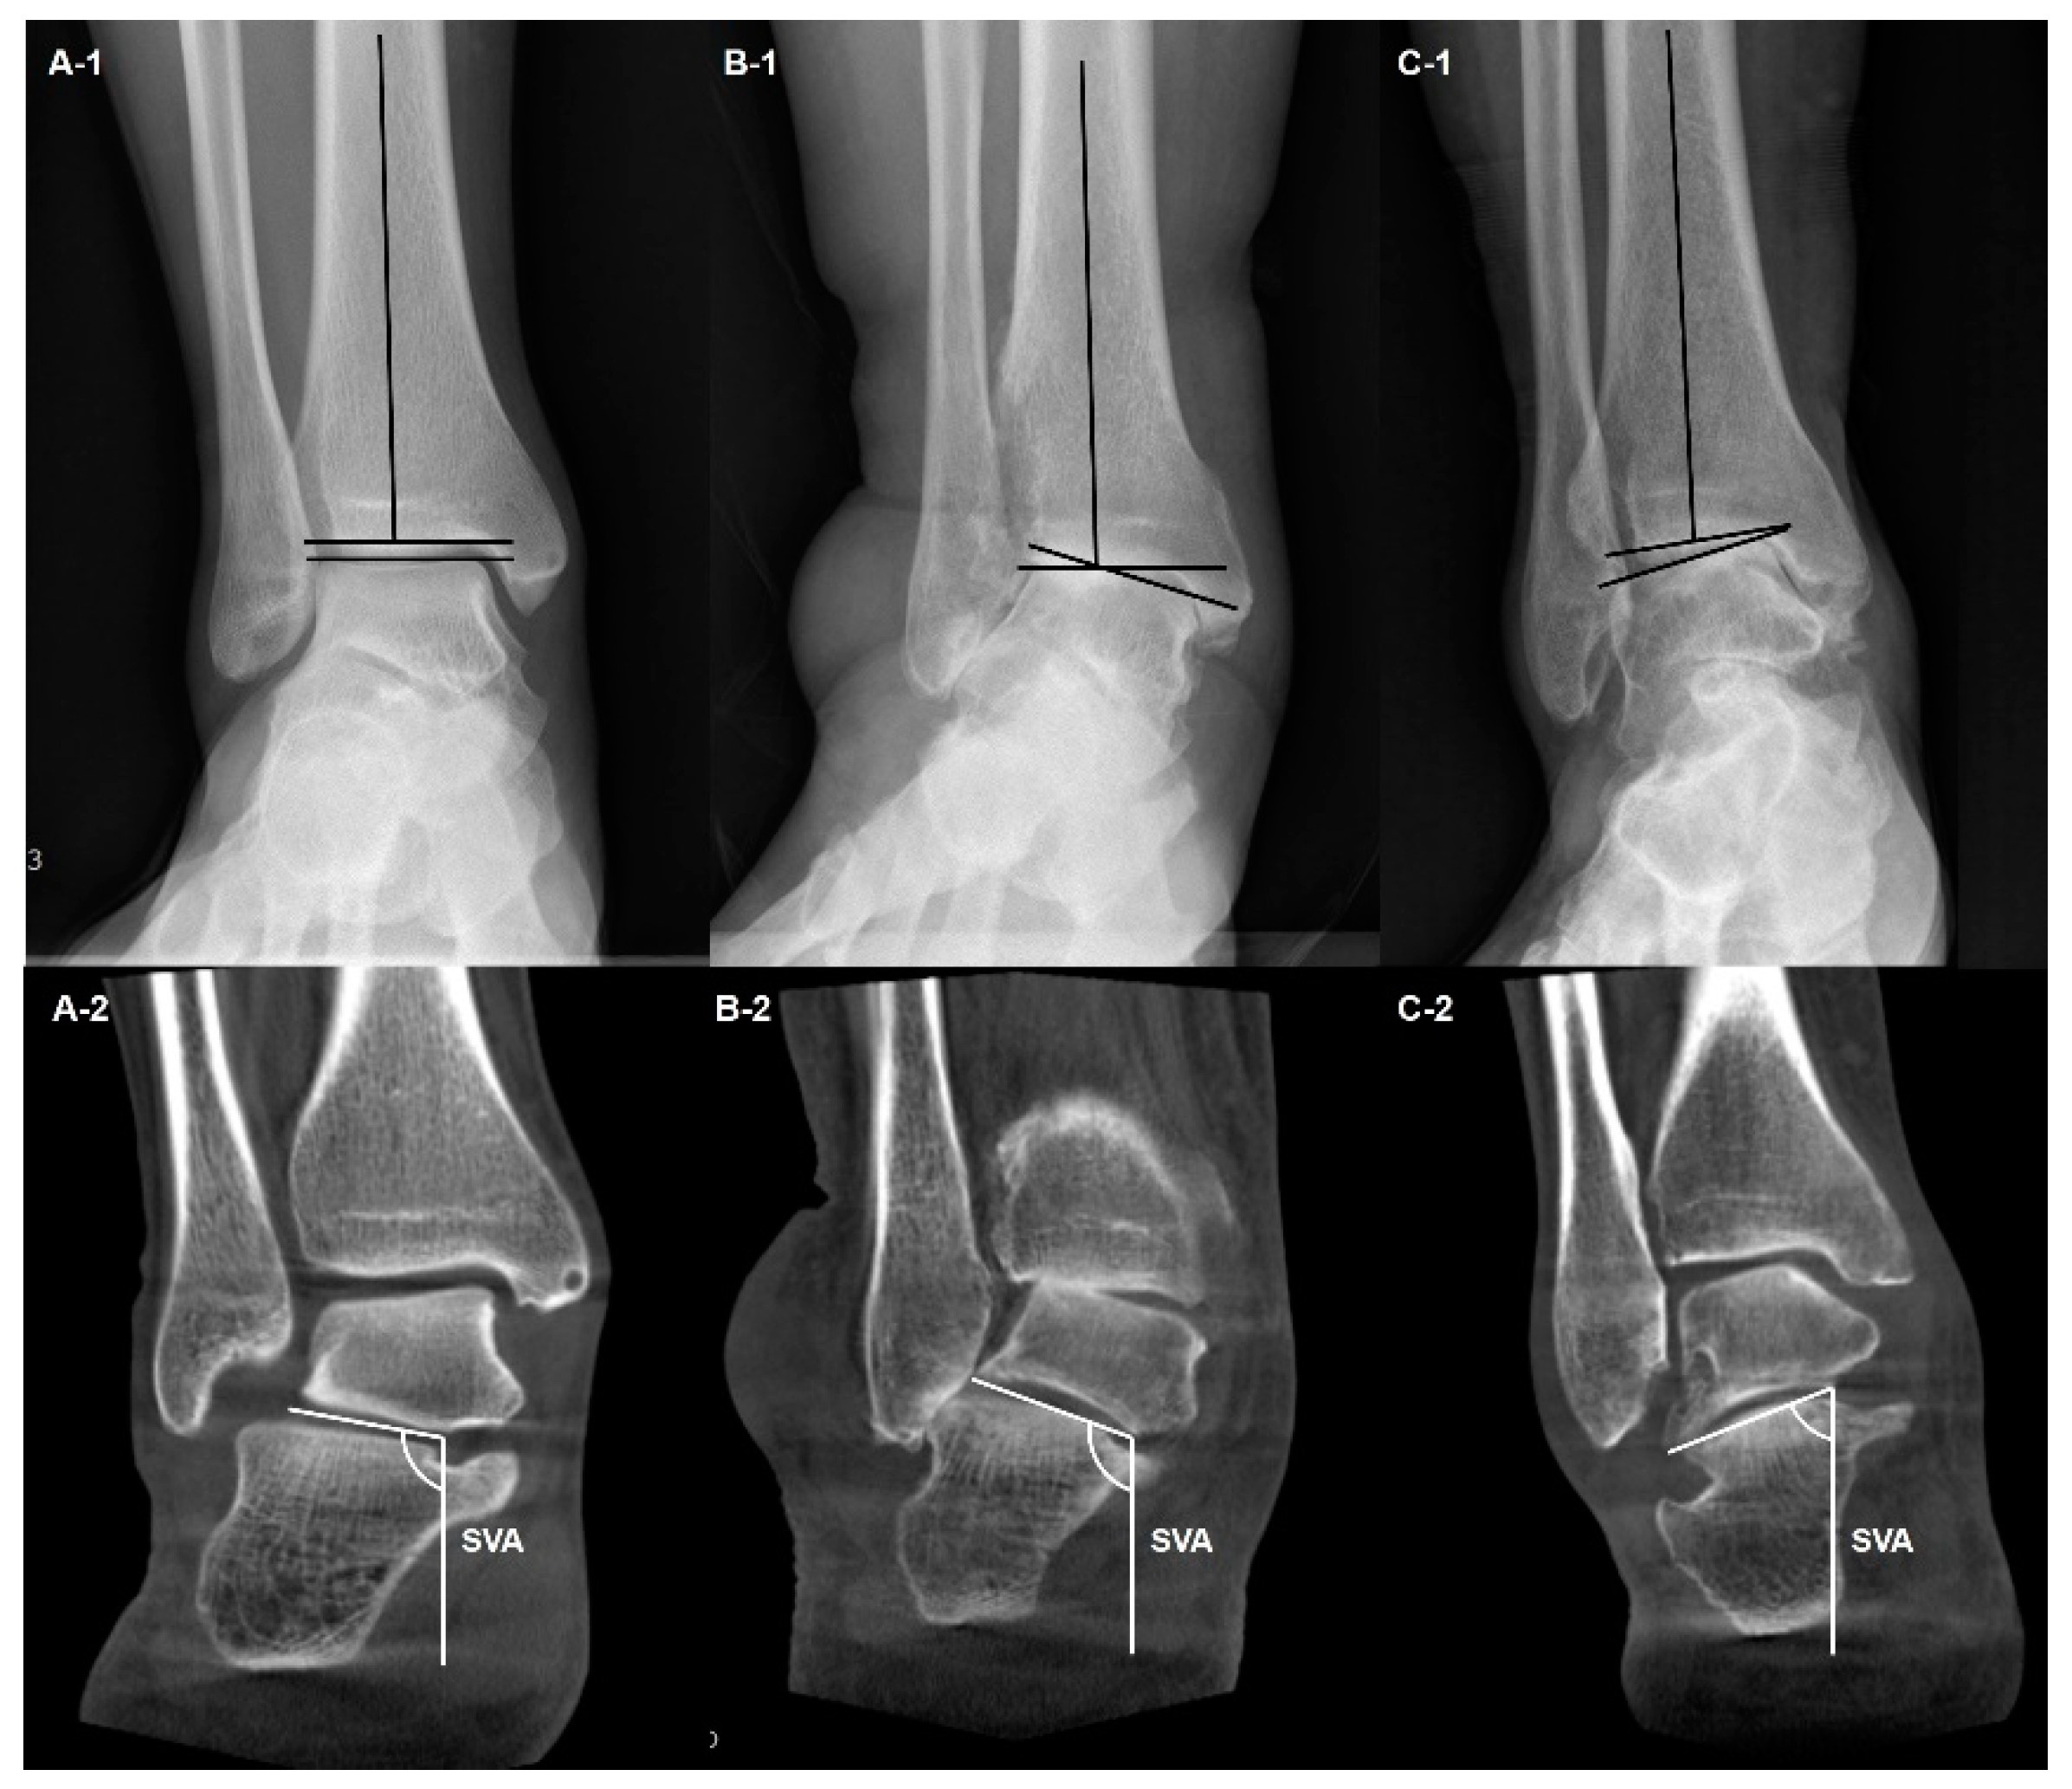

- Song, J.H.; Kang, C.; Kim, T.G.; Lee, G.S.; Lee, J.K.; Ahn, K.J.; Kim, D.H.; Lee, S.W. Perioperative axial loading computed tomography findings in varus ankle osteoarthritis: Effect of supramalleolar osteotomy on abnormal internal rotation of the talus. Foot Ankle Surg. 2021, 27, 217–223. [Google Scholar] [CrossRef]